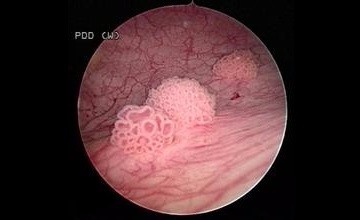

膀胱肿瘤

膀胱癌是指发生在膀胱黏膜上的恶性肿瘤。是泌尿系统最常见的恶性肿瘤,也是全身十大常见肿瘤之一。占我国泌尿生殖系肿瘤发病率的第一位,而在西方其发病率仅次于前列腺癌,居第2位。2012年全国肿瘤登记地区膀胱癌的发病率为6.61/10万,列恶性肿瘤发病率的第9位。膀胱癌可发生于任何年龄,甚至于儿童。其发病率随年龄增长而增加,高发年龄50~70岁。男性膀胱癌发病率为女性的3~4倍。

我科目前根据患者具体情况可选择:膀胱肿瘤电切术、钬激光膀胱肿瘤切除术、红激光膀胱肿瘤切除术、腹腔镜下全膀胱切除术等手术,辅以膀胱灌注化疗、放疗、热疗等综合治疗方案,不同病情的患者均能得到适合的治疗。